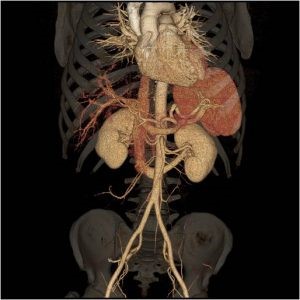

Our section performs and interprets the entire gamut of advanced diagnostic abdominal and pelvic imaging across multiple modalities, including computed tomography (CT), magnetic resonance imaging (MRI), ultrasound, radiography, and fluoroscopy. Our protocols are all encompassing and wide-ranging, including both common and organ-specific complex indications for medical imaging. This includes complete oncologic diagnosis and staging, inflammatory bowel disease, trauma evaluation, emergency radiology, transplant evaluations (such as liver, kidney, pancreas, and bowel), post-operative assessment, genitourinary and reproductive imaging, placental and fetal imaging, CT colonography, contrast enhanced ultrasound, and 3D imaging.